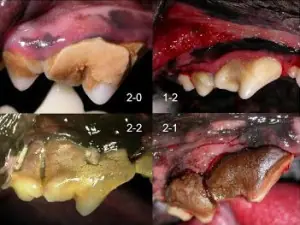

Specifična bolest u mačaka, resorptivna lezija zuba (Feline odontoclastic resorptive lesions (FORLs) je česta u mladih i starijih mačaka te je procijenjeno da više od 70% mačaka ima barem jednu FORL. To je erozija u zubu,uzrokovana djelovanjem odontoklasta (stanicama koje uzrokuju razaranje zuba) najčešće kod granice sa desnima (na vratu zuba), no može biti i niže. Uzrok ove bolesti je nepoznat i teško ju je dijagnosticirati.

Važnost higijene zuba i usne šupljineČesto je potrebno mačku pregledati pod anestezijom. Može se uočiti kao da mala količina desni raste iz zuba, a zapravo su desni upaljene i reagiraju ispunjenjem nastale erozije zuba. Dijagnosticira se RTG-om ili sondiranjem zuba u općoj anesteziji. Takvi zubi su jako osjetljivi i mačke pokazuju bol prilikom dodira, bezvoljne su i otežano uzimaju hranu. Ukoliko se ne liječi, vremenom dolazi do propadanja krune i pucanja zuba, no korijen ostaje unutra. Zub zahvaćen FORL-om treba izvaditi, u protivnom se bolest širi na okolne zube, i drugog liječenja na žalost nema.